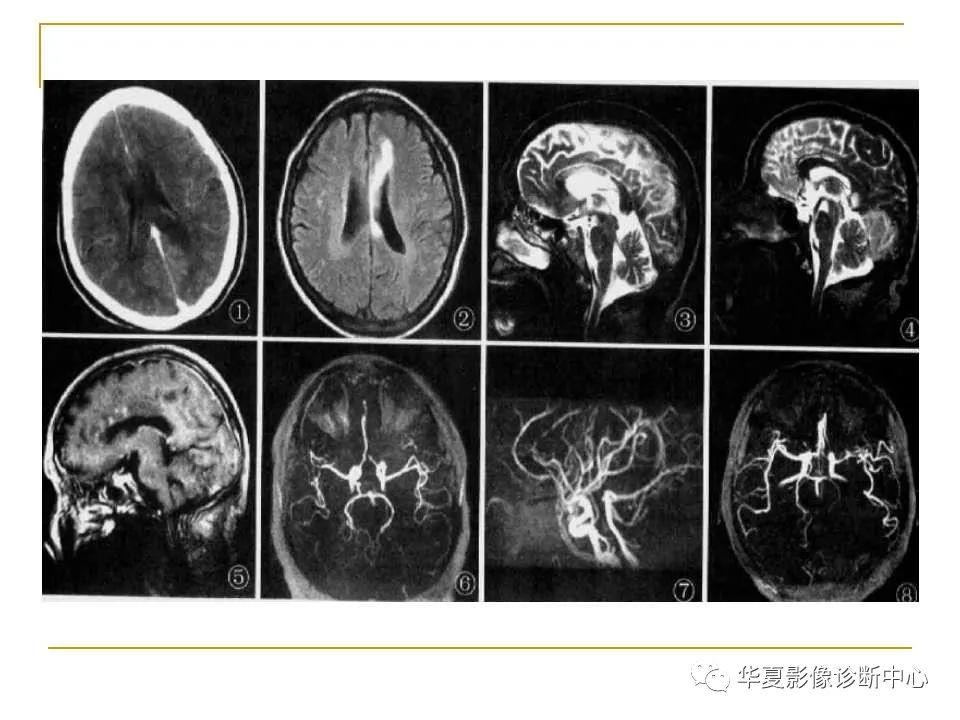

胼胝体解剖及病变大全